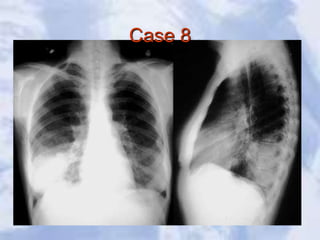

Case 8

Pneumonia:a large pneumonia consolidation in the right lower

lobe. Knowledge of lobar and segmental anatomy is important in

identifying the location of the infection